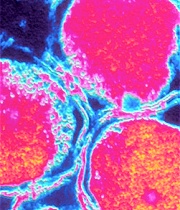

![]() |

| Clamidia, la "infección silenciosa". |